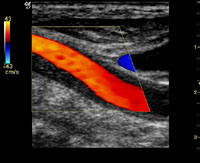

頸部動脈エコー